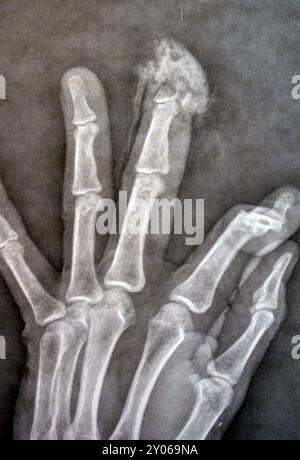

Plain X-Ray reveals distal tip amputation of distal phalanx of the

Plain X-ray Reveals Distal Tip Amputation Stock Photo 2499162053